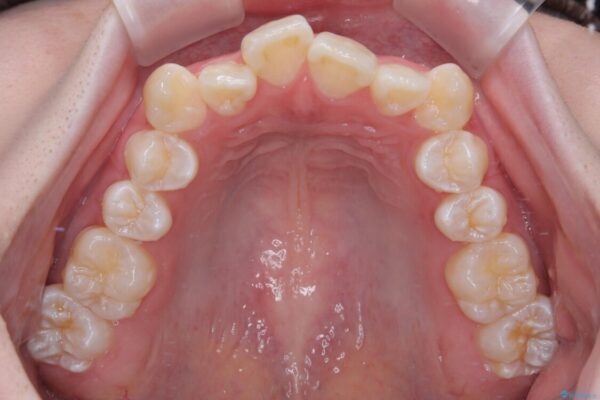

「前歯のデコボコ(叢生)をきれいに整えたい」とのことでご来院されました。

治療前

• 【モニター】前歯のデコボコをスッキリ解消!目立ちにくいワイヤー矯正でスピーディに治療完了 治療前画像